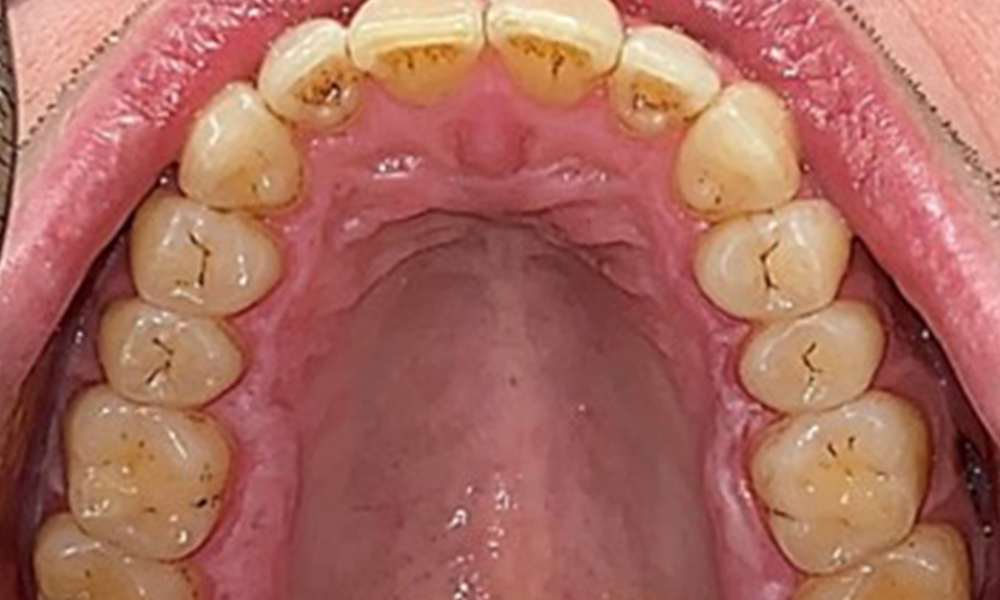

Occlusal view of the maxilla.

Fig. 3: Occlusal view of the maxilla, © Dr R. Krapf

There were no pathological extraoral findings. During intraoral examination, inspection of the frontal view revealed brownish discolouration near the keratinised gingiva and at the transition to the moveable mucosa (Fig. 2), which could be attributed to nicotine consumption. Whitish mucosal lesions were observed on the palate, particularly near the maxillary molar palatal surfaces, indicating increased keratinisation and can also be attributed to nicotine consumption. The tongue was covered with a removable white and brownish coating.

The patient has full dentition with a total of 28 teeth. There were noteworthy erosions and attritions. (Fig. 4, Fig. 5). Due to bruxism, the patient has been wearing a splint with an adjusted bite block at night for many years. The erosions were caused by long-term consumption of isotonic beverages. No periodontal bone loss or active caries were observed.